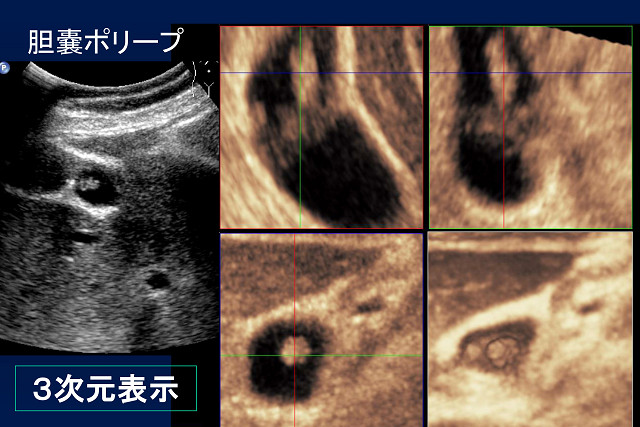

大きな関心事だと思います。「がん」はその最たるものですが、エコーではカラードプラ法が

威力を発揮するということを、画像を示して説明していただきました。

血流の向きと速さをカラー画像で表示することにより、多血性か乏血性かで、腫瘍の種類を

区別することができるというお話でした。